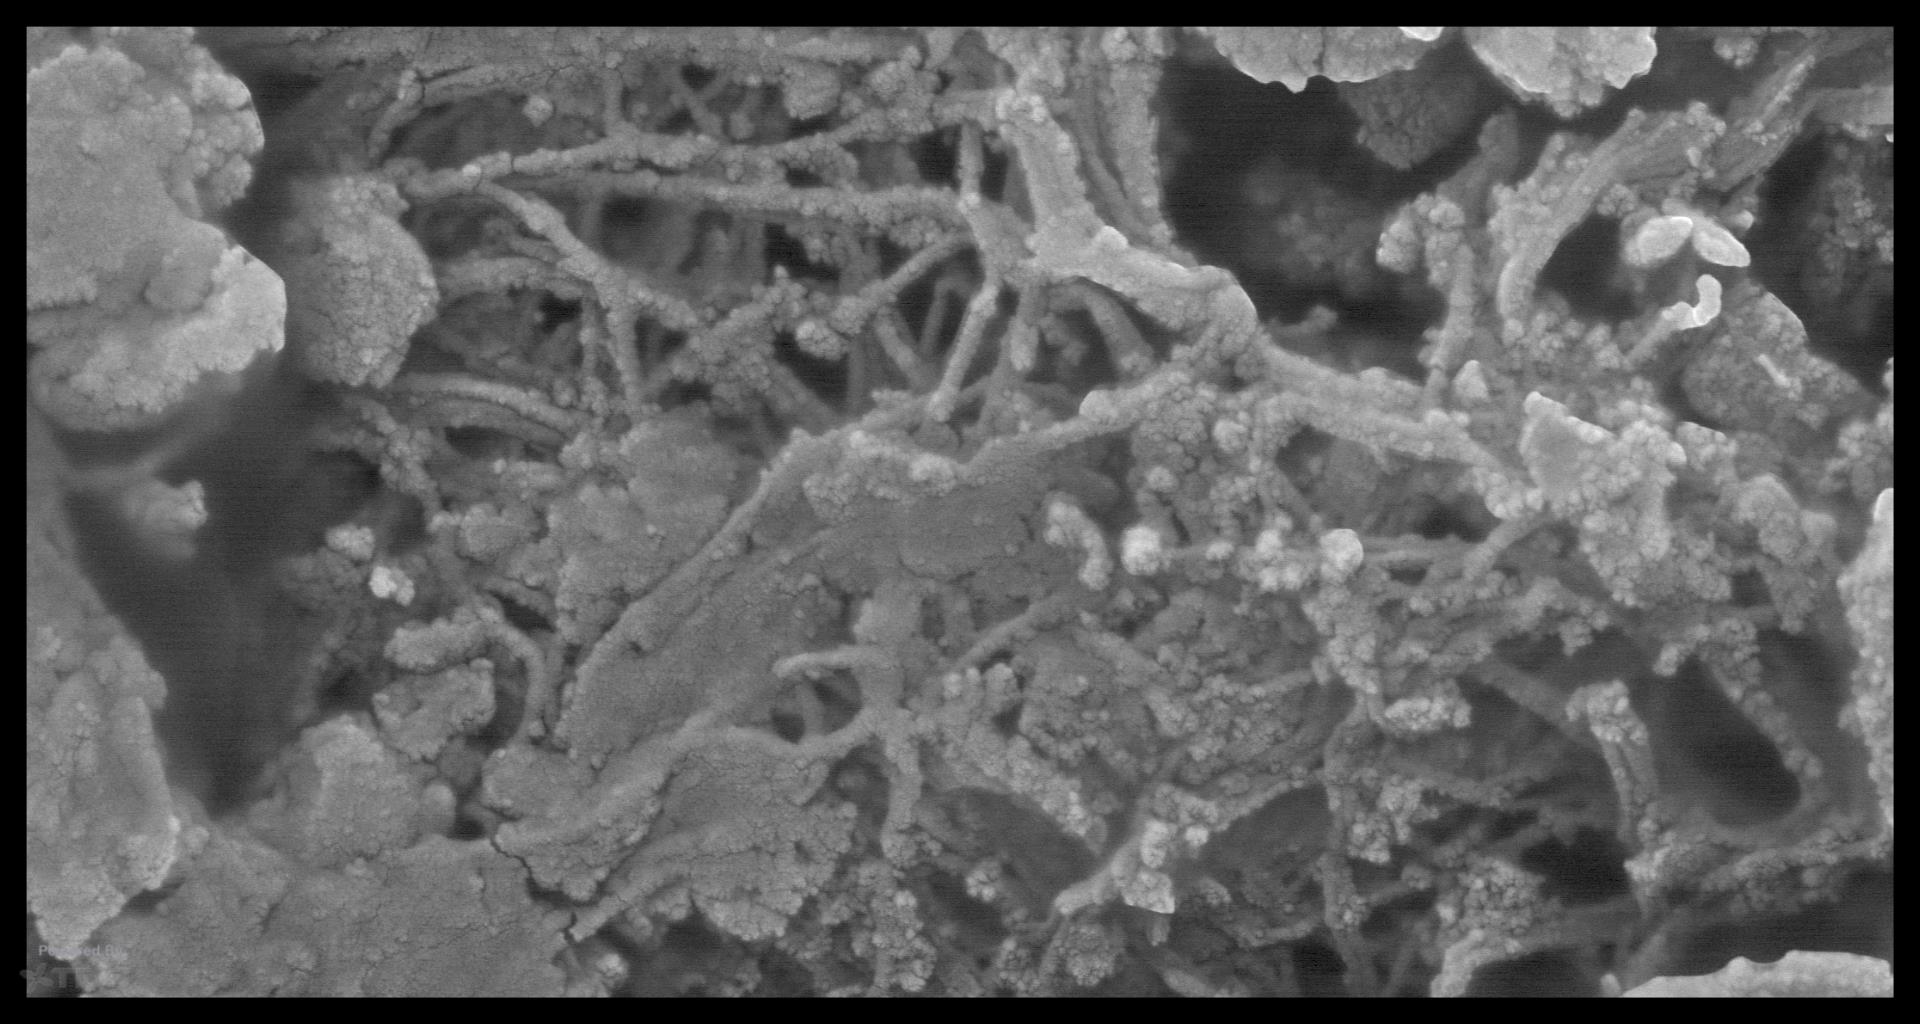

In looking at the GW effect, I did some preliminary work in trying to see the effect of EDTA and NaOCl on dentin—something I was only remotely familiar with. Anyway, just from a scientific perspective, when you decalcify dentin at various time frames, you can see how the collagen protein itself must act as the nucleation site for the apitite crystal to form. Although Ca and Phosphorus are present in the extracellular fluid, the actual orgaizing of the apitite structure appears to be controlled by the spacial structure of the collagen molecule. In the various stages of decalcification you can see here, it is clear the collagen must be controlling the process and you can see the calcospherites almost forming before your eyes. Probably not of great interest to a lot of endodontists but to me…. Always fascinated by the unique structure of dentin…. gbc